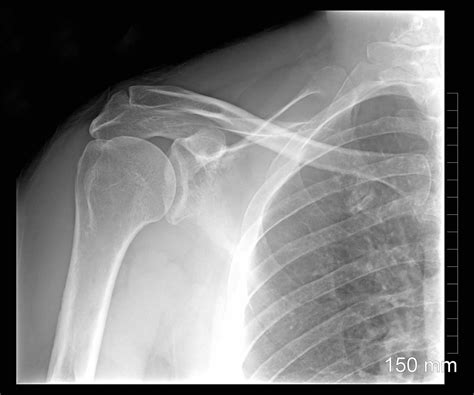

Imaging studies play a crucial role in visualizing the epiphysis and identifying any abnormalities. X-rays are often the first-line imaging modality, as they can reveal fractures, dislocations, and bone deformities. However, X-rays may not always be sufficient to visualize subtle cartilage or soft tissue injuries. In such cases, more advanced imaging techniques like magnetic resonance imaging (MRI) may be necessary. MRI provides detailed images of the epiphysis, including the growth plate, articular cartilage, and surrounding soft tissues. This can help diagnose conditions like osteochondritis dissecans, cartilage damage, and occult fractures that may not be visible on X-rays. In some cases, computed tomography (CT) scans may be used to assess complex fractures or bone tumors involving the epiphysis. CT scans provide cross-sectional images of the bone, allowing for precise evaluation of fracture patterns and bone structure. Additionally, laboratory tests may be ordered to rule out infections or inflammatory conditions that can affect the epiphysis. Blood tests can help detect elevated white blood cell counts, inflammatory markers, or abnormal levels of calcium, phosphate, or vitamin D. In summary, diagnosing epiphyseal problems requires a comprehensive approach that integrates clinical findings with imaging and laboratory data. This allows healthcare professionals to accurately identify the underlying cause of the problem and develop an appropriate treatment plan. Getting the right diagnosis is the first step towards effective management and preventing long-term complications!